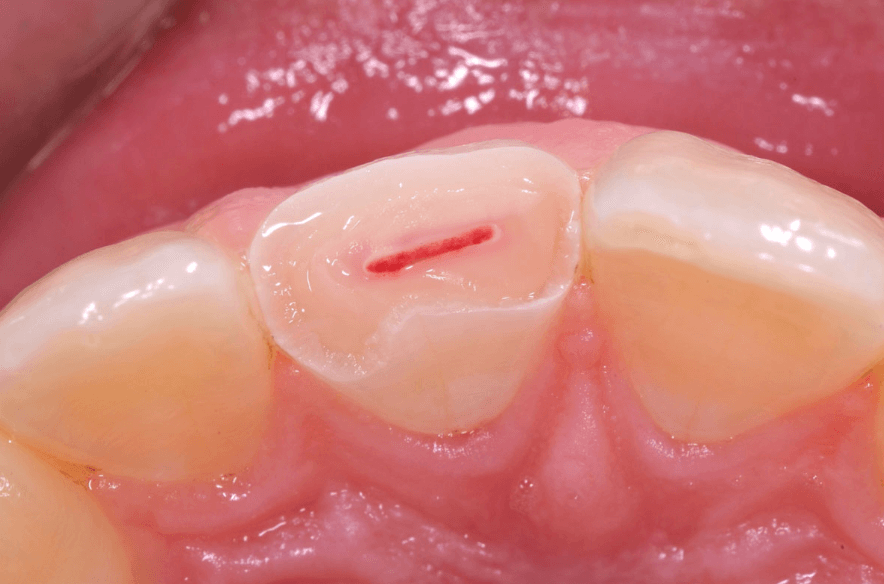

⚠️ 가만히 있어도 욱신? 신경 손상 가능성

신경까지 손상된 경우입니다. 이 경우, 신경치료가 필요할 수 있습니다(출처: https://atlasdental.ca/dental-pulp-capping/)

깨진 뒤

가만히 있어도 통증이 지속되거나 😰

밤에 더 아프고

열감이 느껴진다면

치아 안쪽 치수(pulp)까지

손상이 갔을 가능성이 있습니다.

이 경우는

단순 보강이 아니라

신경치료가 필요할 수 있어요.

통증이 ‘잠깐’이 아니라 ‘지속적’이라면 반드시 확인이 필요합니다.